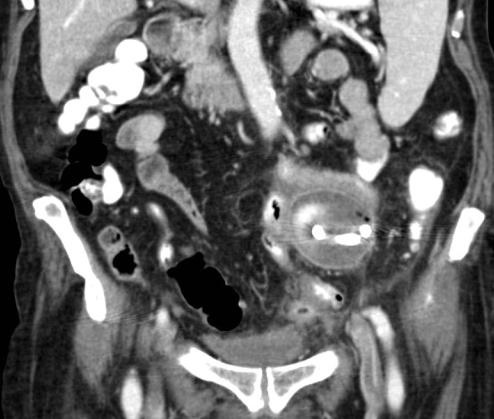

导致肠脓肿的原因可能有手术肠切除,吻合口瘘,或炎性疾病导致肠穿孔,尤其是憩室炎,阑尾炎,以及Crohn病。 在许多这类病人中都会出现脓肿和肠道的连接,宽泛地定义为瘘管形成。 认识到瘘管的存在是很重要的,如果提前拔除脓腔引流管会导致脓肿复发,除非脓腔同肠道的交通闭合。诊断存在交通对确定脓肿形成的原因也很重要,这样能够更好地放置导管使之有利于交通的闭合,并且能够确定适宜的营养支持方式。有了现代技术的支持,肠道脓肿的治愈率可以达到70-90%。 如果存在肠道交通,可以在CT上看到气体,口服或直肠注入的造影剂溢出腔外,或是在积液内部存在长的气液平面,积液临近肠管,以及存在已知的胃肠疾病。可以在插入导管3-5天后进行脓腔造影证实诊断,因为这时候可以用造影剂使脓腔充盈而没有造成菌血症的危险。将导管放在合适的位置上注射造影剂,并且对腔内任何“鸟嘴样”的区域在透视下经引流管的成熟窦道用适宜的普通导管进行小心地探查,常常可以提示存在交通,否则这样的交通常常被忽略。有时候,交通在引流后两周还未能显示。 大多数肠道脓肿,包括那些因术后肠道损伤,吻合口瘘,阑尾炎,以及憩室炎导致的脓肿,都以一个低排量的“瘘管”有关,每天的引流量小于100mL。这种脓肿一般对PAD反应良好,前提是基础的肠管是健康的,并且能够自行愈合。导管的位置应该能使侧孔尽量接近交通的开口,但脓肿其它的部分也应该得到引流。对于大多数病例,一根引流导管就可以达到目的了,但有时必须使用两根以上的引流导管。病人一旦退热,就可以出院,门诊病人可以每7-14天作一次脓腔造影,直到脓腔的交通愈合。病人在家时应该记录导管的引流量。 对有高排量“瘘管”的脓肿进行PAD时需要更长时间,更大强度的治疗,而成功率却较低。必须排除潜在的肿瘤性病因,并且必须进行适宜的肠腔造影检查排除远端肠道梗阻。可以通过胃造瘘或鼻胃管或鼻空肠管控制肠道分泌。如果交通的瘘管从小肠的近端发出,而空肠营养管的远端可以放置在瘘口以远从而保证没有返流会进入瘘管,这种情况下就可以经肠给予营养。如果不是这样,就应该开始全肠外营养。必须严密地监测电解质平衡和代谢状态。可以将一根大管径的引流槽引流管放入脓腔的游离部分,把另一根导管放在瘘管的开口处,或最好是放在瘘管内堵塞这个通道,这样就完成了PAD。 随后,用一根小管径的导管更换这根导管,然后慢慢地将其撤出,使脓腔愈合。这种情况需要延长导管引流的时间,在开始引流后12周才会愈合。进行实体器官移植而免疫抑制的病人能够得到成功治疗,但往往需要更长的引流时间。对于那些PAD不成功而需要手术的病人,PAD仍然起到了暂时治疗和改善临床状态的作用。 病例1 42岁,睾丸癌病史,Lynch 综合征 II期(pT3c N0 M0)进行结肠切除和回场-直肠吻合术